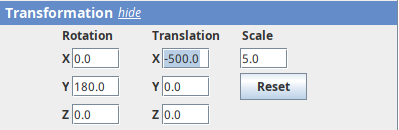

- Now change

Scaleto5andTranslation Xto-500to focus on the nose.